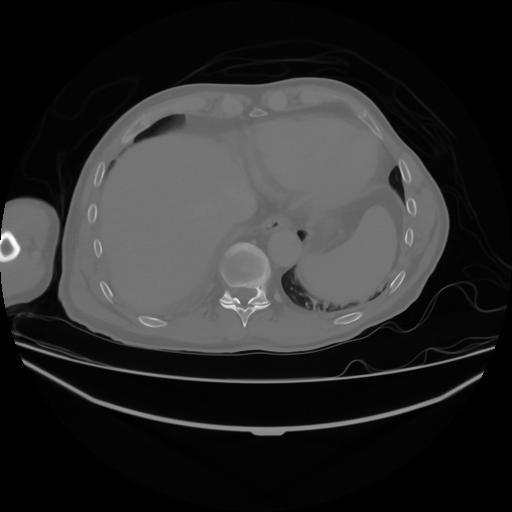

4 CUERPO,CE,Axial,3.0,CUERPO,,